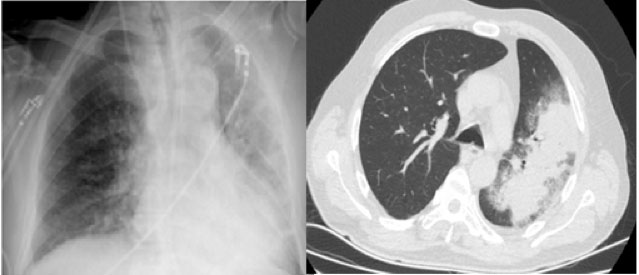

Toraks BT raporu: Sol akciğer üst ve alt lobu yaygın etkileyen içerisinde hava bronkogramları çevresinde buzlu cam dansitesinde alanların eşlik ettiği konsolidasyon alanı izlenmiştir. Ayrıca bu alanlara eşlik eden intralobüler septal kalınlaşmalar ve sentriasiner nodüller dikkati çekmiştir. Bulgular enfeksiyon ile uyumludur. Bakteriyel ve viral nedenler ayırıcı tanıda yer almalıdır.

Nefroloji tarafından hemodiyaliz planlanan hastaya, acil serviste favipravir + meropenem + linezolid tedavisi başlanıyor. Hasta COVID -19 yoğun bakım ünitesine yatırılıyor. Hastanın acil polikliniğine başvurusunda çekilen PA akciğer grafisi ve toraks BT’si Şekil 1’de görülmektedir.

Şekil 1: Hastanın acil polikliniğine başvurusunda çekilen PA akciğer grafisi ve toraks BT’si